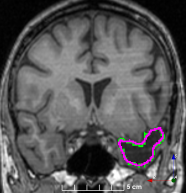

(f)

Figure 3: Manual labels from Rater A (green) and Rater D, the model trained with PubFull + EpiPre + Pseudo (magenta). Errors caused by a (a) small resection, (b) blood clot in cavity and (c) brain shift; segmentations corresponding to the (d) 50th, (e) 75th and (f) 100th percentiles giving a DSC of 81.7, 86.5 and 93.8, respectively.

We trained a model using PubFull, EpiPre and Pseudo (2371 images), obtaining a DSC of 81.7 (14.2). Adding the pseudo-labels to PubFull and EpiPre did not significantly improve performance (p=0.176𝑝0.176p=0.176), indicating our semi-supervised learning approach provided no advantage. Predictions from this model are shown in Fig. 3.

Predictions errors are mostly due to 1) resection of size comparable to sulci (Fig. 6a), 2) unanticipated intensities, such as those caused by the presence of blood clots in the cavity (Fig. 6b), 3) brain shift (Fig. 6c) and 4) white matter hypointensities (Fig. 6e). Further work will involve using different internal and external cavity textures, carefully sampling the resection volume, simulating brain shift using biomechanical models, and quantifying epistemic and aleatoric segmentation uncertainty to better assess model performance [24].